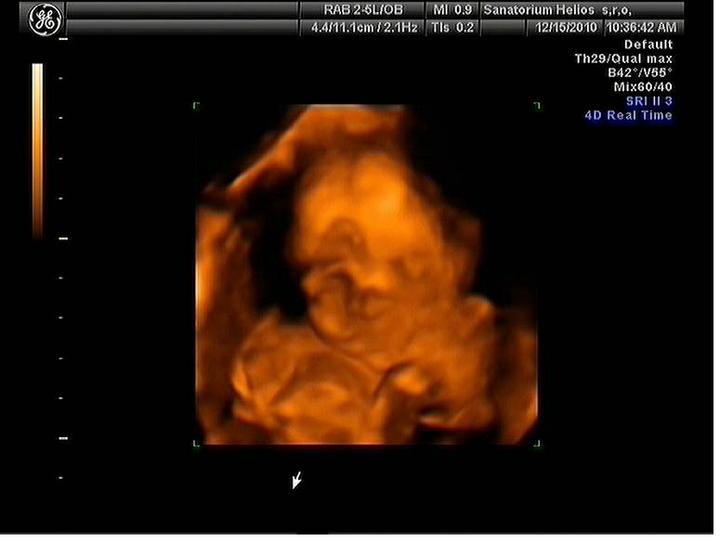

Jsme zpátky z dovolené, prcek v bříšku ani moc nezlobil🙂

Za 7 hodin uvidíme naši fazolku, nemůžu se dočkat a asi proto nemůžu spát. Strašně se těším. Snad bude vše v pořádku.